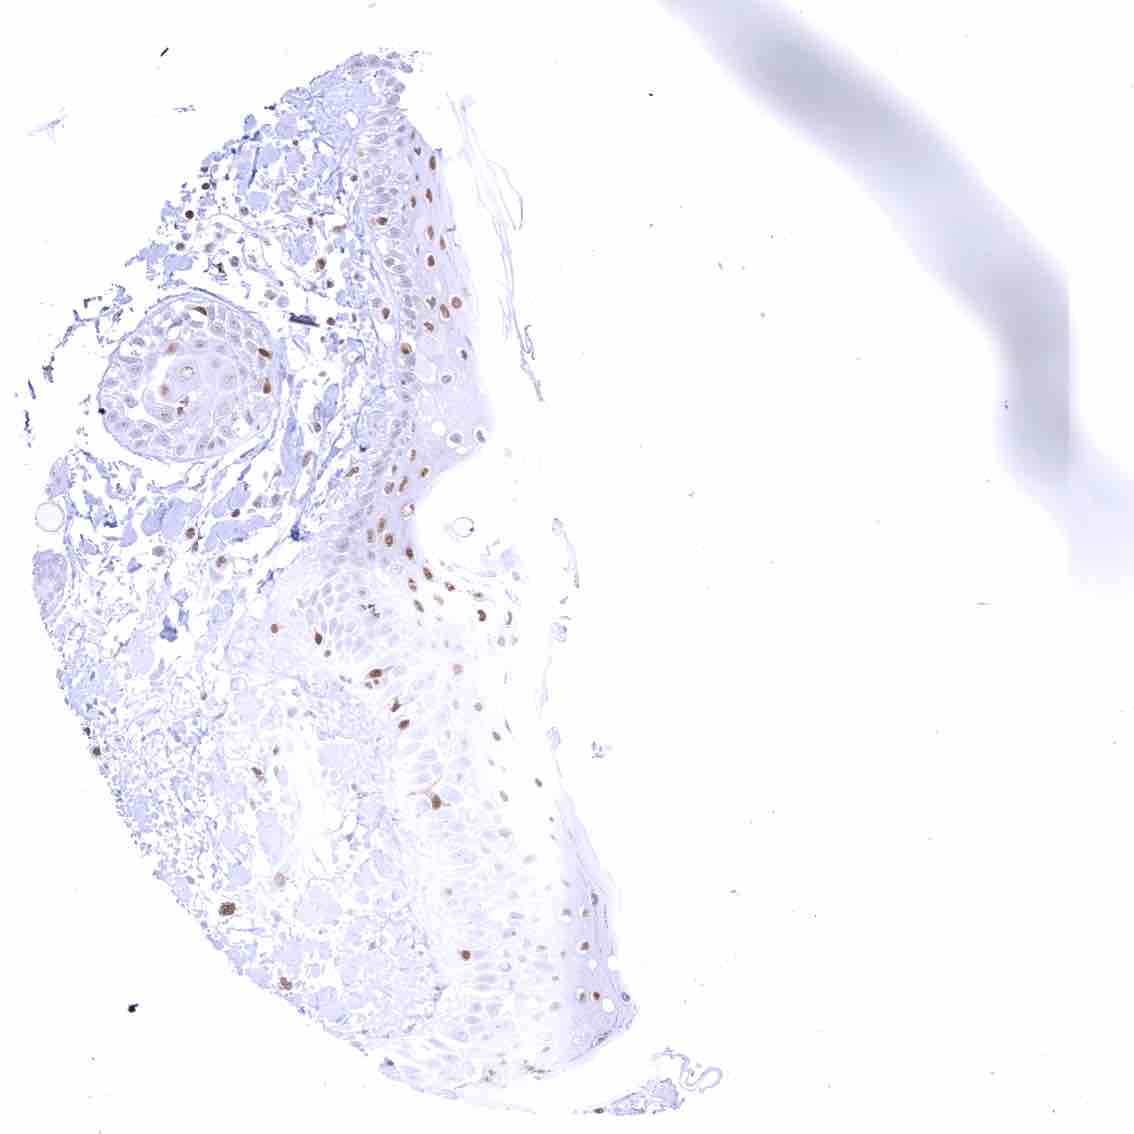

Skin – Moderate to strong nuclear p27 staining occurs in a large fraction of squamous epithelial cells and predominates in the more mature cell layers (top 50_ of the epidermis).

Skin, hairfollicel and sebaceous glands – Moderate to strong nuclear p27 staining in all cells of sebaceous glands. .jpeg